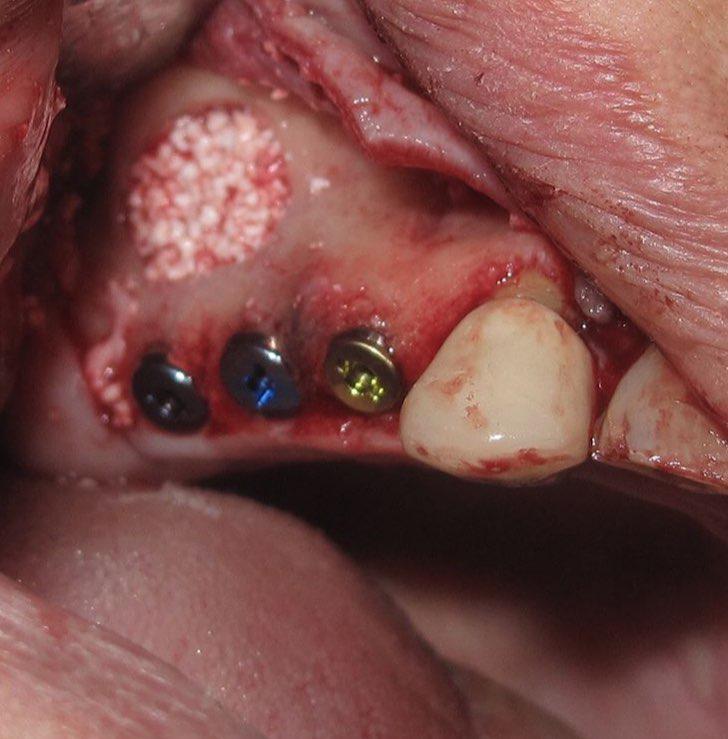

جراحی گذاشتن ایمپلنت های دندانی جهت جایگزینی دندانهای از دست رفته

جراحی پیوند استخوان جهت افزایش میزان استخوان و آماده سازی برای گذاشتن ایمپنت

جراحی سینوس لیفت بصورت باز و بسته برای گذاشتن ایمپلنت